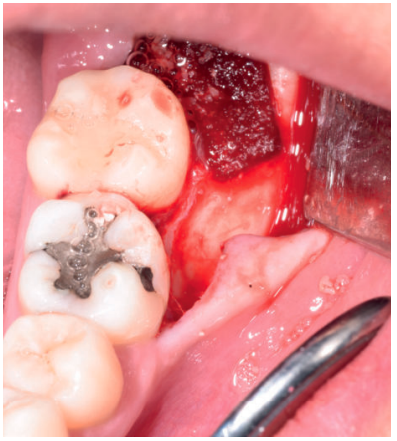

Los fragmentos coronal y radicular se limpiaron de restos de tejidos blandos, y secos, se introdujeron en la máquina Smart Dentin Grinder® (Kometa Bio, BIONER, España). Tras un ciclo de triturado de 3 segundos, y otro de tamizado de 20 segundos, el material obtenido (Figura 3) se limpió con la primera solución durante 12 minutos, y después durante 3 minutos con la segunda solución, para después transportar el material de injerto al alveolo, con presión controlada (Figura 4). Una vez compactado, se colocó una esponja de fibrina (Gelatamp® ) (Figura 5) y se suturó la herida con seda de 4/0, mediante dos puntos simples en la cara distal del segundo molar inferior izquierdo, un punto en cruz en la descarga y un punto en la papila (Figura 6). Se realizó una radiografía periapical intraoperatoria (Figura 7).